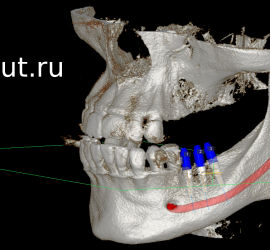

Учебный фильм по планированию имплантации в компьютерной программе EZ3D2009 (Vatech). Фильм по работе с EZ3D2009 можно посмотреть здесь.